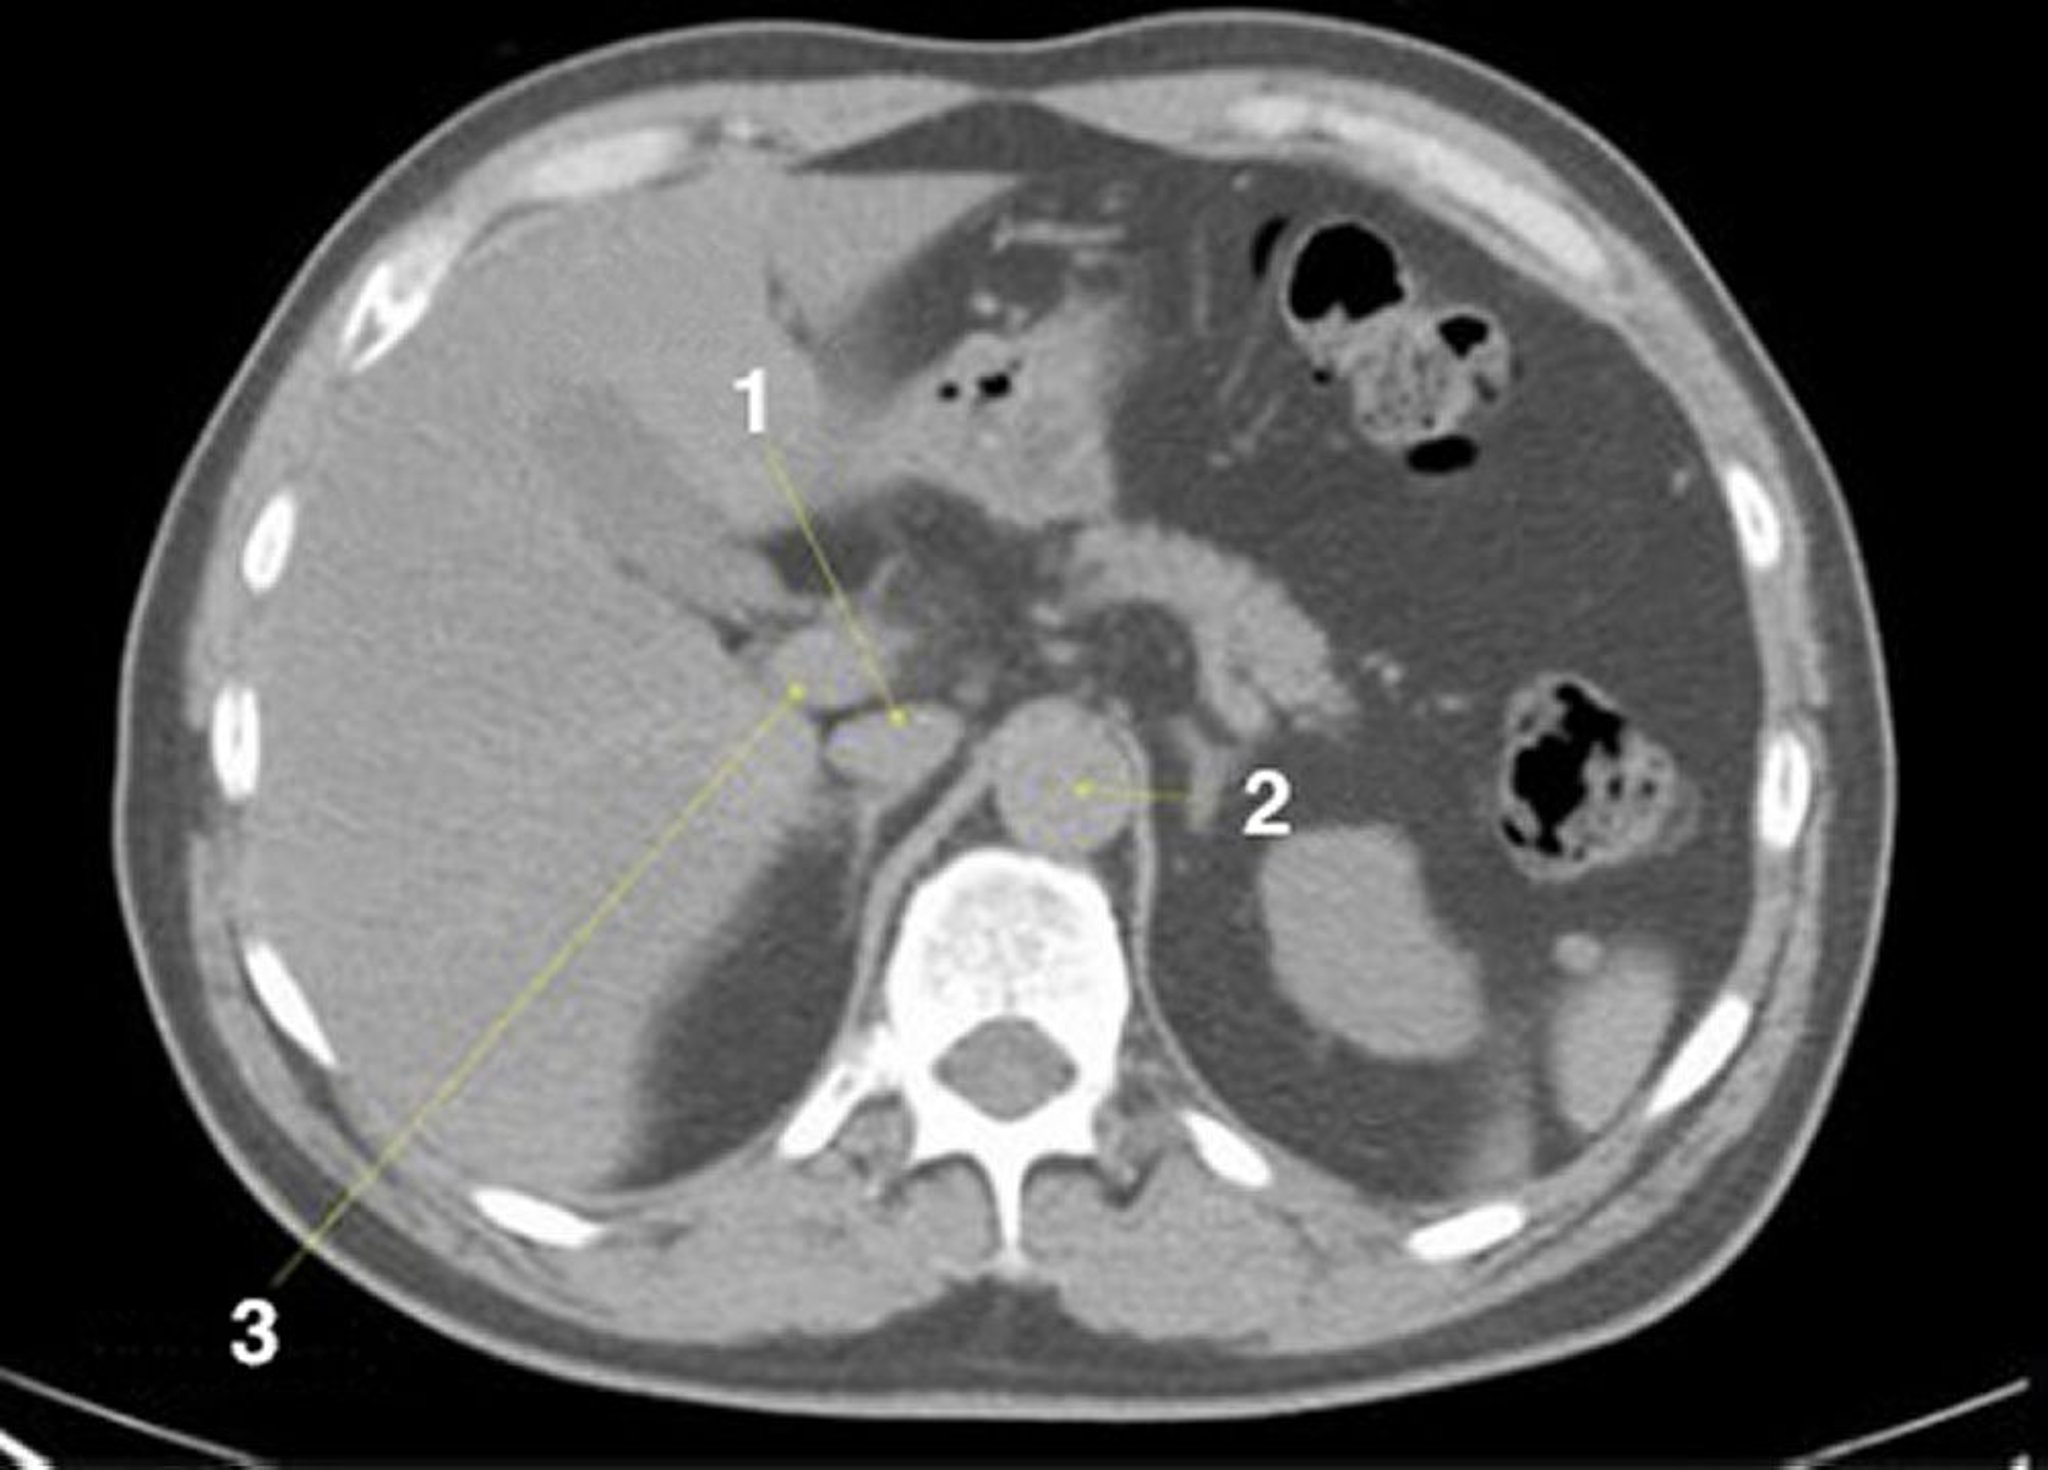

КТ брюшной полости и таза без контраста, демонстрирующая нормальную анатомию (слайд 6)

1 = нижняя полая вена; 2 = аорта; 3 = портальная вена.